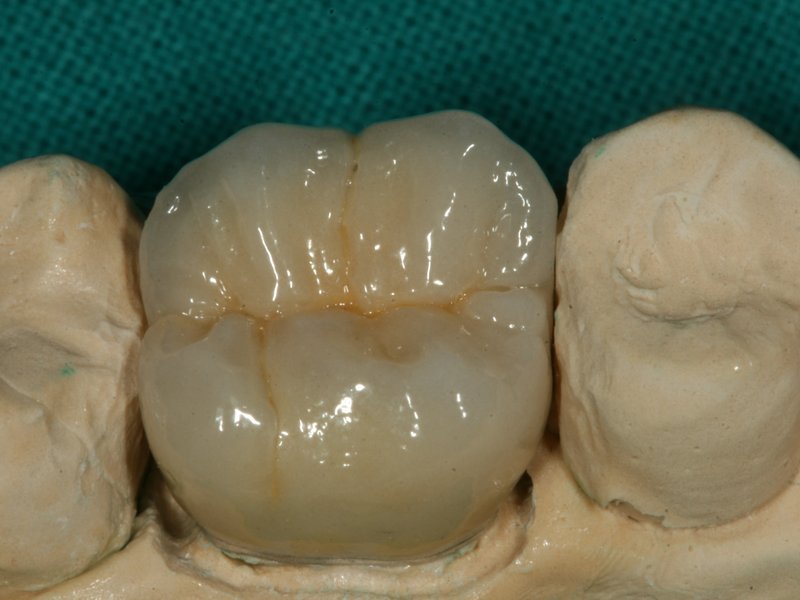

Rozsáhlá nevyhovující amalgámová výplň a vpravo náhrada za keramickou overlay

Keramická overlay nahrazující nevyhovující amalgámovou výplň